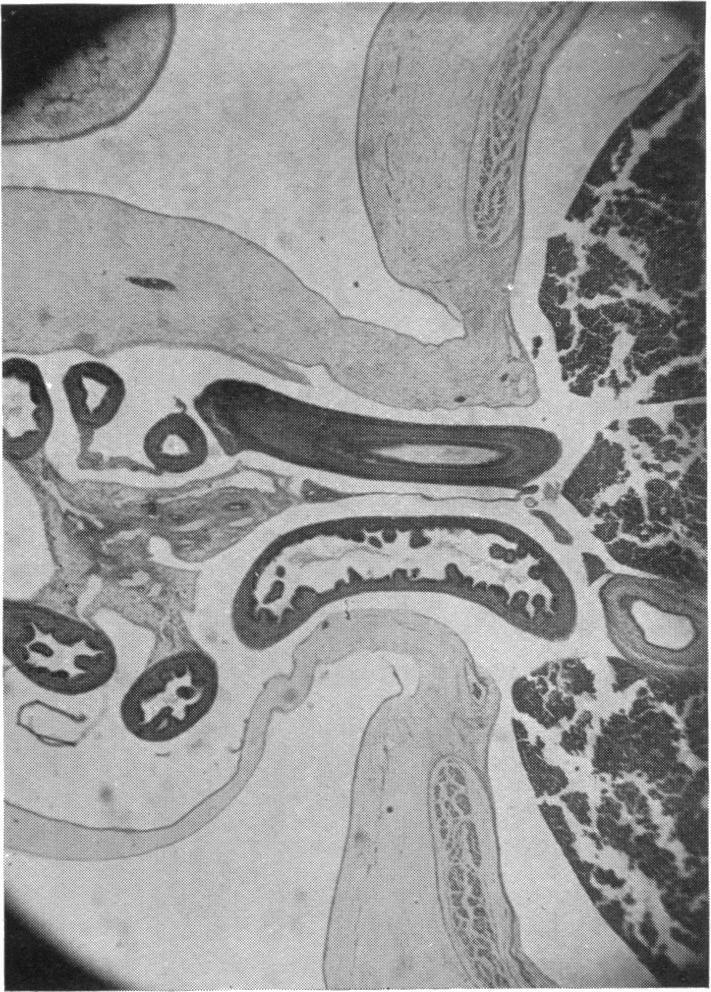

The Development of the Infra-Umbilical Portion of the Abdominal Wall, with Remarks on the Aetiology of Ectopia Vesicae.

J Anat. 1937 Jan;71(Pt 2):201-31.